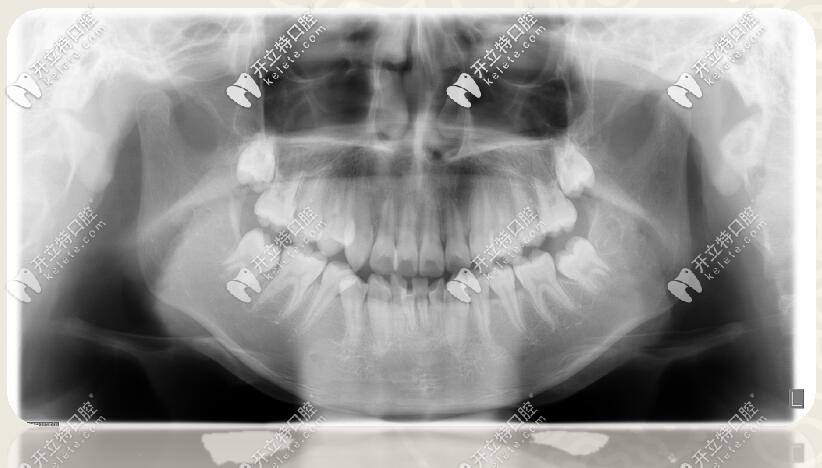

口腔全景片

1、安氏Ⅱ類錯(cuò)合

2、骨性二類錯(cuò)合

3、前牙區(qū)深覆蓋、深復(fù)合

4、跨牙合

5、牙列擁擠不齊